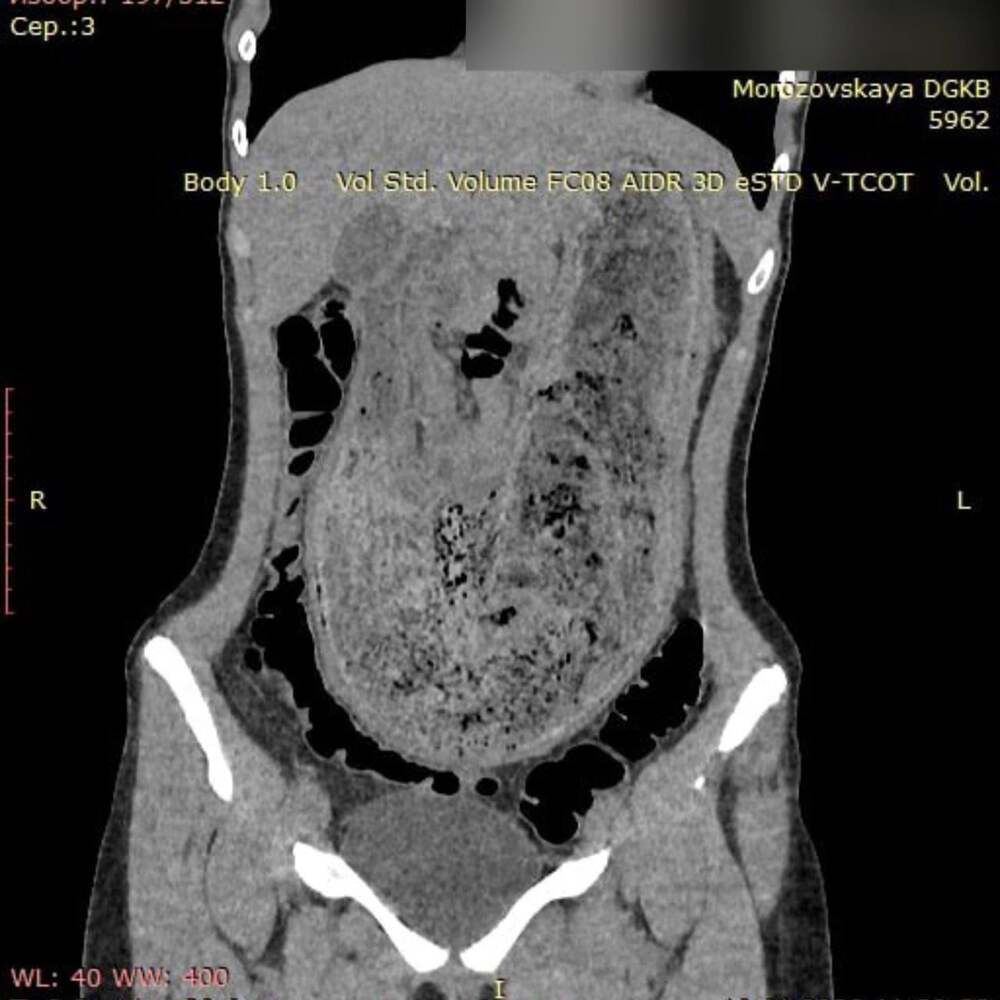

В ГБУЗ «Морозовская детская городская клиническая больница» поступила 17-летняя пациентка в крайне тяжёлом состоянии. Девушку мучили невыносимые боли в животе и постоянная рвота. В ходе обследования врачи обнаружили трихобезоар, заполнивший весь желудок и часть двенадцатиперстной кишки. Как... Далее